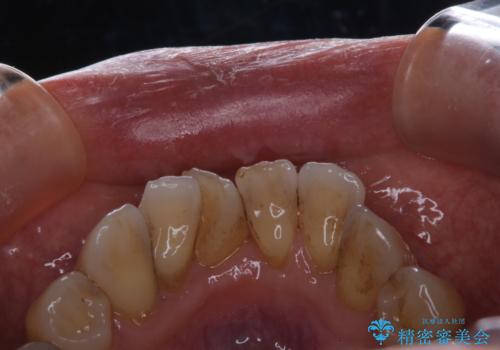

- これから、全体的な総合治療がスタートするため、着色や汚れをきれいにしてほしいとのことでした。PMTC60分コースを行いました。

施術後の歯の表面に、茶色く色が残っている所がありますが、これは詰め物の変色の所と、虫歯になっている所です。以前に、CR(コンポジットレジン)による虫歯治療がされています。

CRは経年的劣化や、着色してしまうことがあります。PMTCでクリーニングを行うと、古いCRが目立つことがあるため、気になる際は詰め替えを行います。

茶色くなっている部分が、着色なのか、劣化なのか、虫歯によるものなのかは判別が難しいことがあります。そのため、定期的にPMTCを行うことで状態の確認が的確に行えます。